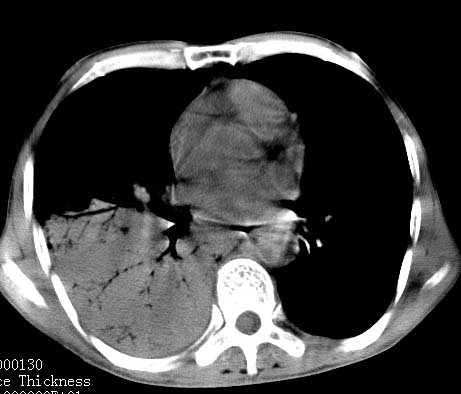

病人女 60岁 咳嗽 气促十余天,大叶性肺炎.

右肺上下叶均见 大片状密度增高影,边界清晰,其内可见支气管充气征,气管支气管通畅。纵膈略向右移位,其内无肿大淋巴结影。首先考虑炎性病变。不排除一些特异性的炎症。不知道发烧吗??wbc高吗??建议治疗后复查!!

看影响还是首先考虑炎性改变,建议实验室检查,还有要警惕炎性肺泡癌,具有的枯枝征象。

右肺感染性病变(大叶性肺炎可能);建议抗炎治疗后复查。

看影像还是首先考虑炎性改变,建议实验室检查,还有要警惕炎性肺泡癌,具有的枯枝征象